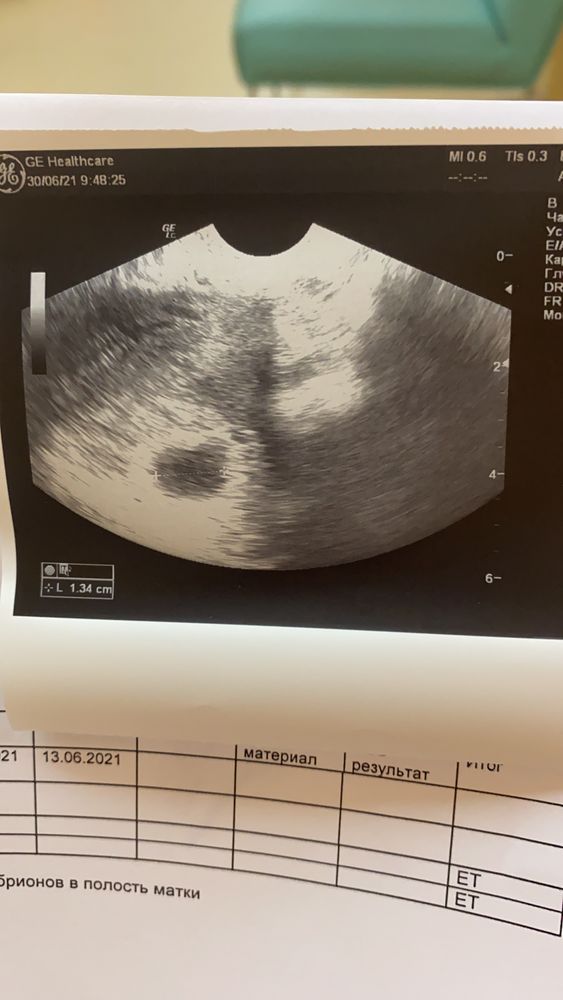

21 дпп 30.06.21 - наконец-то наступил мой отпуск, всего 10 дней, но последнее время тяжело даются поездки на автобусе на работу, дорога занимает 1,5 часа и, возможно, из-за этого меня преследуют выделения. Утром заметила, что соски стали очень чувствительными, сегодня первое узи: плодное яйцо 12мм, желточный мешочек есть, эмбриона пока не видно, в остальном всё в норме.